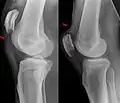

X-ray of a tear of the patellar tendon. On the left: The kneecap is pulled up. On the right: Significant dent in the soft tissue above the kneecap.